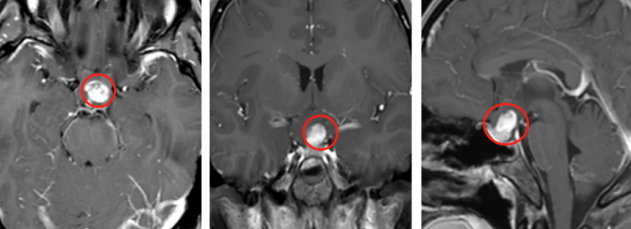

一名6岁的女童在视力检查出现问题后被转介到眼科。经检查,她的左眼视力下降(20/80)和色觉(仅限控制板)。右眼视力和色觉正常。她有一个低振幅,高频摆...

视神经胶质瘤(ONG)是较常见的原发性视神经肿瘤,通常在生命的一个十年被发现。散发性视神经胶质瘤(OPGs)通常在8岁前出现。我们的病人是ONG文献中一个没...

视神经胶质瘤手术后视力还能恢复吗?孤立性视神经胶质瘤是一种少见的视神经通路胶质瘤。由于这种情况的少见性和在大多数临床系列中很难区分孤立性...

与非手术治疗相反,手术可以立即消除眼球突出和疼痛,在眼球运动和眼睑抬高方面具有良好的美容效果,是在早期未进行放疗的情况下。对于所述儿童视...